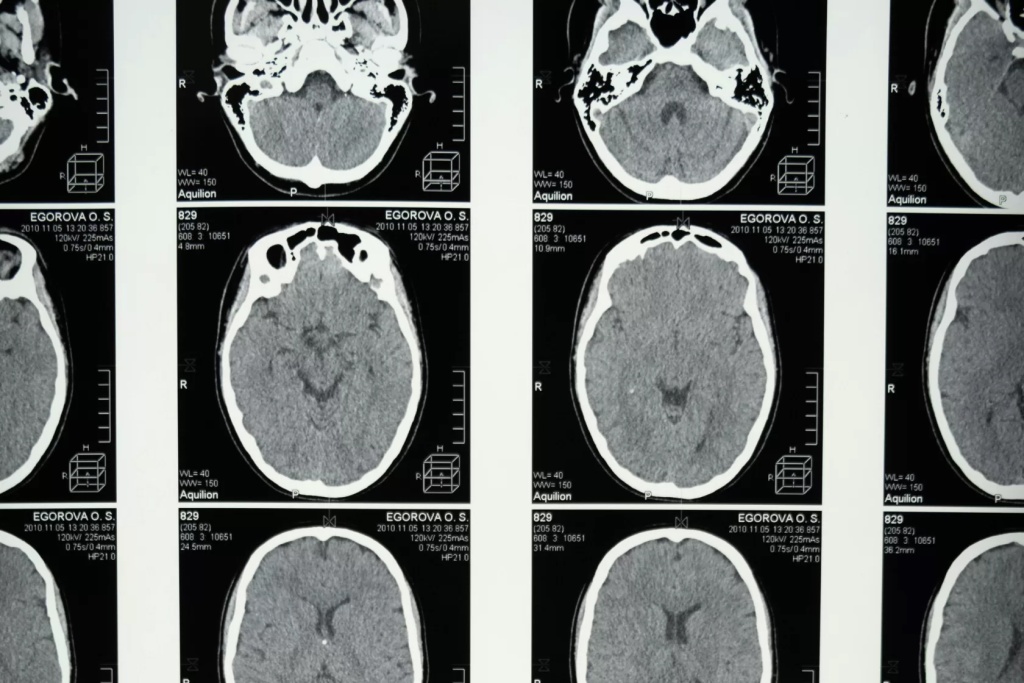

Предположим, у пациента обнаружили подозрительные изменения в тканях мозга на рентгеновских снимках. Для более точной диагностики врач назначает ему МРТ. Благодаря пониманию режимов МРТ, радиолог способен выбрать оптимальные параметры сканирования, что позволит получить высококачественные изображения мозговых структур с высоким разрешением. Это поможет точно определить характер и стадию заболевания и разработать наиболее эффективный план лечения для пациента.

В диагностике режим Т1-взвешенной МРТ широко применяется для обнаружения опухолей, кровоизлияний, инфарктов и других изменений в мягких тканях организма. Этот метод также полезен для оценки состояния мозга, позвоночника, суставов и органов грудной клетки.

Рассмотрим ситуацию, когда пациент обращается к врачу с жалобами на головные боли и головокружения. Врач назначает ему МРТ головного мозга в режиме Т1-взвешенной последовательности для выявления возможных патологий. После анализа полученных изображений врач обнаруживает опухоль в головном мозге, что позволяет начать своевременное лечение и повышает шансы на успешное исход.